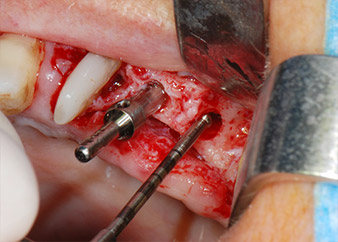

En el siguiente paso, los lechos del implante se prepararon en las posiciones 25 y 26 con instrumentos rotatorios, utilizando un contra-ángulo con un coeficiente de transmisión de 20:1 (WS-75 L, W&H), junto con el nuevo potente motor de implantes Implantmed de W&H (figuras 8 y 19).

La preparación final junto al seno se realizó de nuevo con un inserto piezoeléctrico (Piezomed S2).

A continuación, los implantes (Restore, Keystone Dental, 3,75 mm de diámetro, 8,0 mm de longitud) se colocaron con el motor de implantes (figuras 11 y 12).